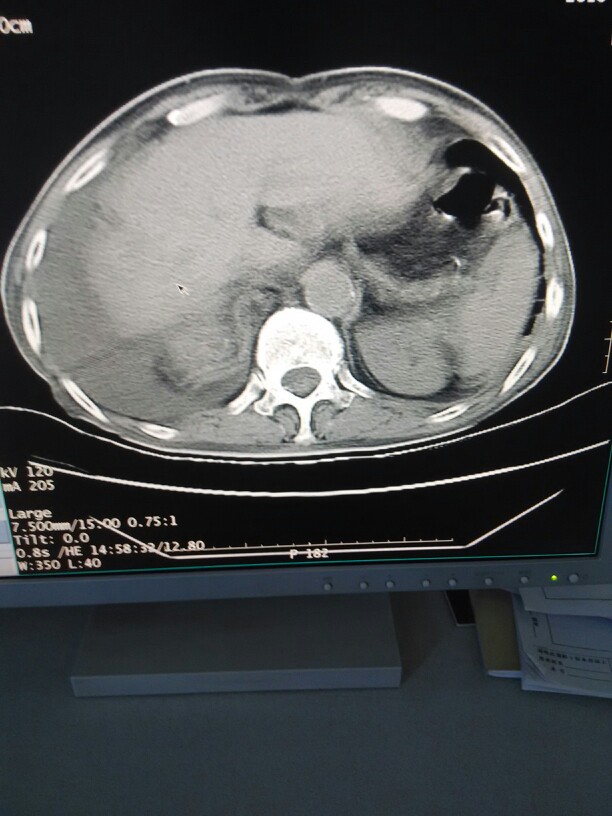

食管裂孔疝 ( hiatus hernia;esophageal hiatal hernia )